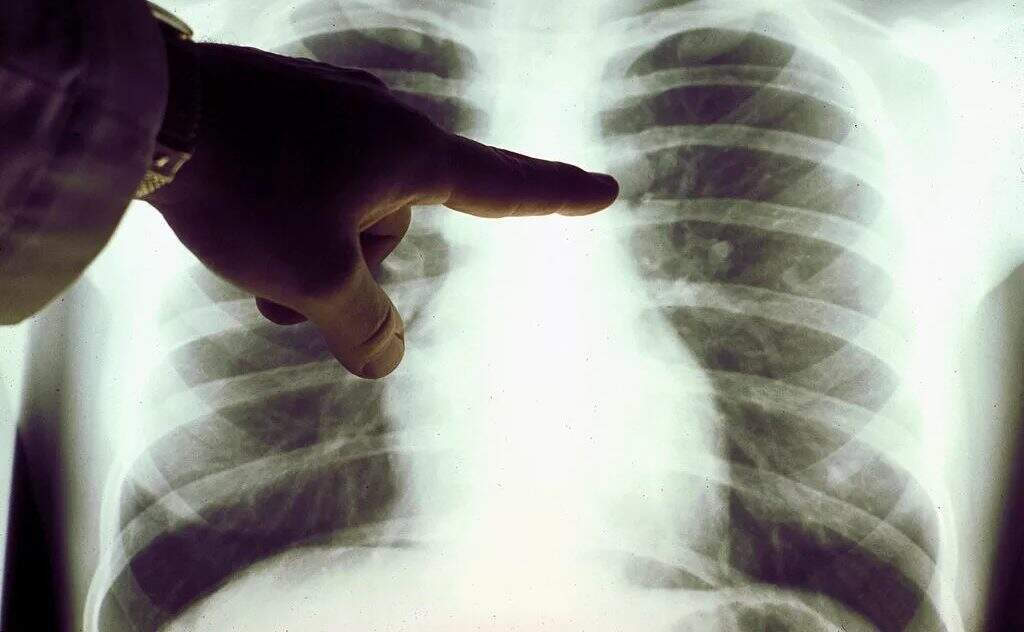

“A profissional que fez a tomografia saiu de trás daquela parede e vidro e me perguntou: ‘Você veio aqui por quê?’ Respondi que era porque minha tosse não passava. Questionei se tinha dado algo no exame, e ela me respondeu que minha médica falaria comigo. No mesmo dia a secretária da pneumologista me ligou dizendo que a médica queria falar naquela tarde. Fui no consultório. A médica me mostrou a tela do computador e estava tudo branco, dos dois lados. Questionei o que era aquilo e ela disse que provavelmente era câncer. Aí o meu chão abriu. Porque, até então, tudo o que você sabe sobre esse tipo de doença que é que você vai morrer rápido.”

O câncer de pulmão é o segundo tipo de tumor mais comum no País e atinge cerca de 30 mil brasileiros por ano. Dados do Instituto Nacional do Câncer (Inca) apontam que o tabagismo é responsável por cerca de 90% dos diagnósticos desse tipo de tumor. Não há dúvidas de que o principal fator de risco para a doença é o tabagismo. Por isso, a grande maioria dos casos está concentrada em fumantes ou ex-fumantes. Entretanto, casos como o de Astur têm se tornado mais comum no mundo todo e a tendência chama a atenção de especialistas.